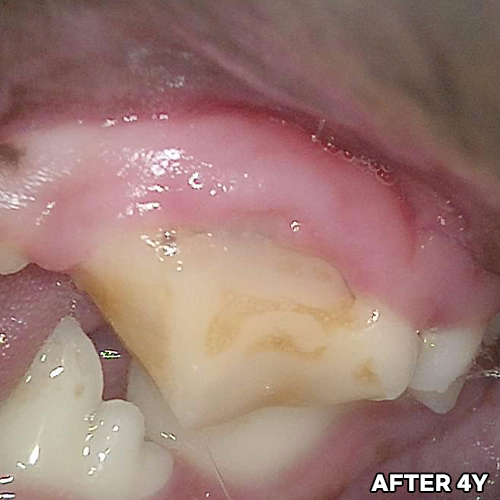

[강아지 치아파절 치료 후 4년 경과모습]

샘플